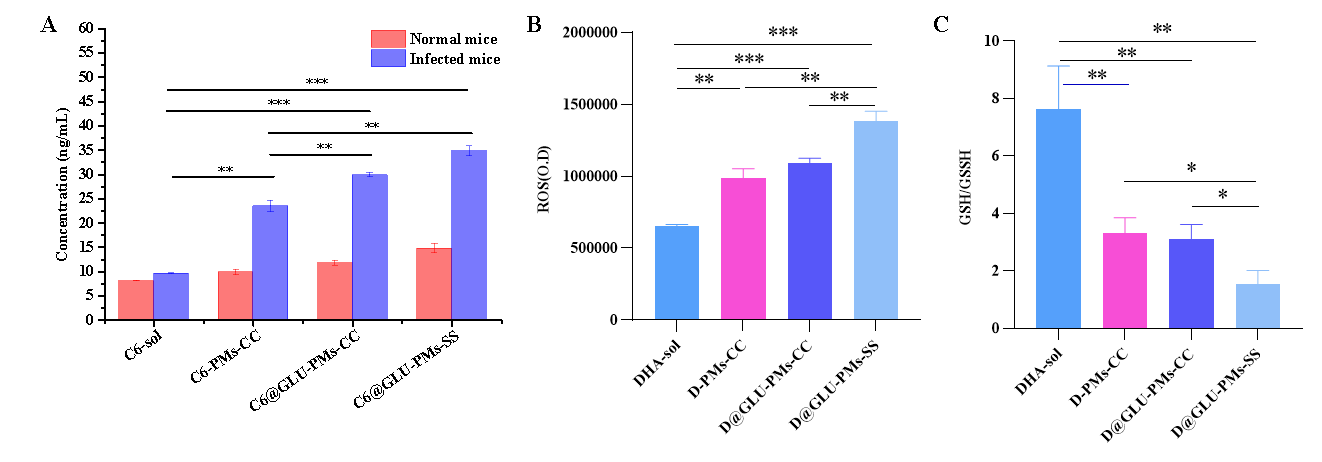

图3 C6-PMs-CC����、C6@GLU-PMs-CC和C6@GLU-PMs-SS的红细胞内靶向性(A)评价����;DHA-sol���、D-PMs-CC����、D@GLU-PMs-CC和D@GLU-PMs-SS作用后红细胞内的ROS(B)和疟原虫内的GSH/GSSG比值(C)的测定(n = 3)

将C6标记的微粒注射到疟原虫感染的小鼠体内���,C6@GLU-PMs-CC组感染小鼠红细胞中的C6含量(11.81 ng/ml ± 0.54 ng/ml)明显高于 C6-PMs-CC 组(9.97 ng/ml ± 0.50 ng/ml)(P<0.05)(图3A)���。将微粒与受感染的红细胞在体外进行共孵育��,D@GLU-PMs-SS组中红细胞中的ROS和疟原虫中的GSH/GSSG比值分别是D@GLU-PMs-CC对照组的1.27倍和0.49倍(图3AB)���。